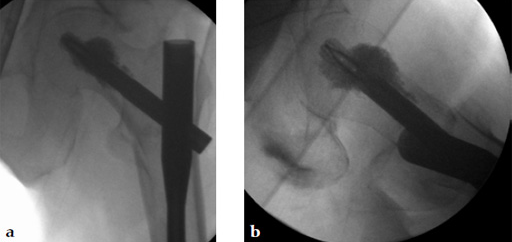

After finishing the usual procedure of inserting the nail and the perforated blade, a leakage into the joint has to be excluded by injection of contrast medium through the perforated blade first. Then the prefilled side opening cannula is inserted into the blade and the position checked by image intensifier. A medial perforation must be avoided. Furthermore, the special 1 ml syringe is adapted to the cannula (Fig 6) and the cement can be injected (Fig 7). By turning the cannula the positioning of the cement around the helical blade can be navigated. Around 36 ml of cement should be injected. The whole injection procedure must be done under image intensifier control.